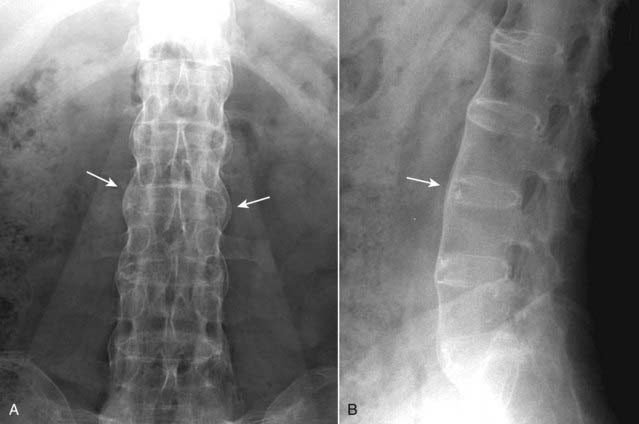

image In the spine, ossification of the outer fibers of the annulus fibrosis produces thin, bony bridges from the corners of one vertebra to another called syndesmophytes. Progressive syndesmophytes production connecting adjacent vertebral bodies produces a bamboo-spine appearance (Fig. 23-20).

Figure 23-20 Ankylosing spondylitis, frontal (A) and lateral (B) spine.

In the spine, there is ossification of the outer fibers of the annulus fibrosus producing thin, bony bridges joining the corners of adjacent vertebrae called syndesmophytes (solid white arrows). Progressive ossification connecting adjacent vertebral bodies produces the bamboo-spine appearance seen in this case, which is characteristic of ankylosing spondylitis.